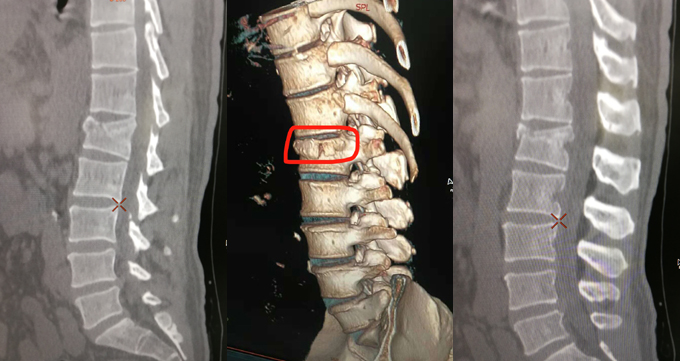

图2:2018年11月17日腰伤CT扫描片(中图为3D建模图)

拱腰内运,促进循环,太极拳是卧床康复的绿色天使。一个多小时后,在惠安县医院急诊,CT扫描结果“腰1骨折”(如图2)。CT侧片显示:腰1骨折,一侧已错开移位,另一侧“入”字深度裂痕。骨科医生会诊提出保守治疗方案“硬板床平躺静养3-4个月”。腰伤初期3天,腰胯甚是酸痛,不得动弹,大便难解(同病房腿伤病友已10天未解)。医生要求同轴侧翻,预防久卧生疮。我尝试着平躺练功,聆听无极桩心法引导音乐,全身放松,意想拱腰滚腰,两肘随“意腰”翻转而动,没练多长时间,感觉腰背慢慢温热,疼痛缓解许多,当天下午就顺畅排便,医护人员感到意外,邻床病友甚是羡慕。住院期间,医护人员每天检查腿脚神经感应及活动力时,我都能用意管控她们,让她们感到腿脚有力并后退。此后,我慢慢地体悟卧床练功要领,腰伤酸痛日渐缓解,腰部活动日渐好转。